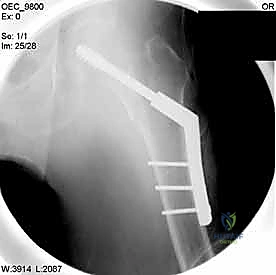

| وجه المقارنة | الشريحة والمسمار المنزلق (DHS - Dynamic Hip Screw) | المسمار النخاعي القريب (PFN - Proximal Femoral Nail) |

| آلية العمل | شريحة معدنية تُثبت على السطح الخارجي للعظم مع مسمار كبير يخترق عنق الفخذ. | مسمار من التيتانيوم يُدخل داخل التجويف النخاعي للعظم (من الأعلى) مع مسامير عرضية للتثبيت. |

| نوع الكسور المناسبة | الكسور المستقرة (Stable Fractures) ذات التفتت البسيط. | الكسور غير المستقرة (Unstable)، المفتتة بشدة، أو التي تمتد لأسفل العظم. |

| الشق الجراحي | شق جراحي جانبي أطول نسبياً (حوالي 10-15 سم). | جراحة طفيفة التوغل، شقوق صغيرة جداً (Minimally Invasive). |

| الميكانيكا الحيوية | يوفر ضغطاً ديناميكياً ممتازاً على موقع الكسر أثناء المشي. | يوفر دعماً ميكانيكياً أقوى لأنه يقع في مركز ثقل العظم (محور تحمل الوزن). |

| فقدان الدم | أكثر نسبياً مقارنة بالمسمار النخاعي. | أقل بكثير. |

| سرعة التعافي | ممتازة، ولكن قد تتطلب حذراً أكبر في الكسور غير المستقرة. | أسرع، ويسمح بتحميل الوزن في وقت أبكر في الحالات المعقدة. |

4. إدخال السلك الدليلي (Guide Wire)

يتم إدخال سلك معدني رفيع جداً عبر العظم باتجاه رأس الفخذ تحت توجيه الأشعة المستمر. هذا السلك يعمل كمسار دقيق سيتبعه المسمار النهائي. يجب أن يكون السلك في الموضع الهندسي المثالي لتجنب اختراق مفصل الورك.

5. الحفر وتثبيت الغرسة (Reaming and Implantation)

يتم استخدام أداة حفر مجوفة تمر فوق السلك الدليلي لتوسيع مسار في العظم. بعد ذلك، يتم إدخال المسمار الرئيسي القوي (سواء المسمار المنزلق أو المسمار النخاعي).

6. التثبيت النهائي (Locking)

لضمان عدم تحرك الغرسة، يتم تثبيتها بمسامير إضافية أصغر في جسم عظم الفخذ. هذه المنظومة الميكانيكية توفر ثباتاً استثنائياً يسمح للمريض بتحريك ساقه فور استيقاظه من التخدير.

مجموعة من الصور الإضافية التي توضح مراحل دقيقة من العمل الجراحي المعقد الذي يجريه الأستاذ الدكتور محمد هطيف لضمان أعلى درجات الدقة الميكانيكية الحيوية: